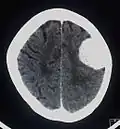

Das bildgebende Verfahren der ersten Wahl ist beim Meningeom heute die Kernspintomografie, da dieses Verfahren den größten Weichteilkontrast besitzt und in typischen Fällen die sichere Diagnose eines Meningeoms ermöglicht. In T2-gewichteten Aufnahmen stellen sich verkalkte Meningeome im Gegensatz zu vielen anderen Tumoren als schwarze Masse (hypointens) dar, die dunkler als das umgebende Hirngewebe ist. Unverkalkte Meningeome können zur Umgebung isointens sein. Von anderen Tumoren unterscheiden sich Meningeome durch ihre Lage auf der Dura mater mit charakteristischen Ausläufern in die Dura (dural tails) und durch eine sehr intensive Kontrastmittelaufnahme. Die Computertomographie kann die Tumorverkalkungen sehr gut nachweisen. Konventionelles Röntgen und Angiographie haben heute nur noch eine untergeordnete Bedeutung.

Kontrastmittel aufnehmendes Meningeom der linken Hemisphäre in der Computertomographie -

Großes Felsenbeinmeningeom in der Computertomographie -